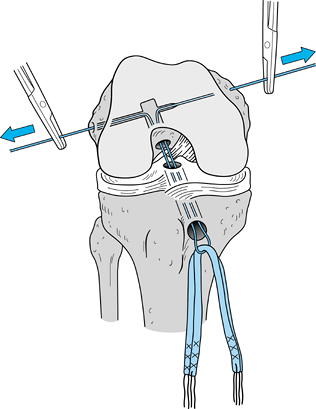

Make the incision (Fig. 89.4)

Figure 89.4.

View of a right knee. Make the incision slightly medial to the midline,

from the distal tip of the patella to 2 cm below the tibial tubercle,

approximately 8 cm in length. Placement of superomedial, inferomedial,

and inferolateral portals is depicted as well. Should the graft

harvesting occur before arthroscopy, place the inferomedial and

inferolateral portals through the graft harvest incision. -